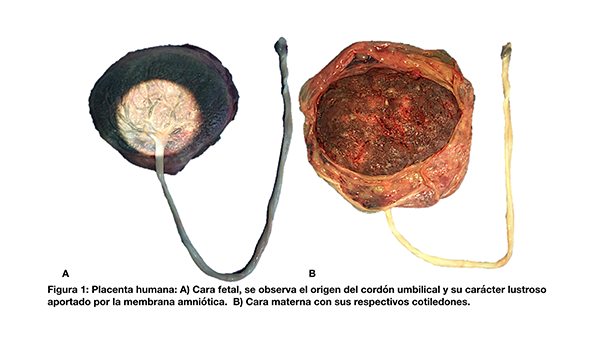

La placenta humana (del latín torta plana) es un órgano endocrino discoide de carácter transitorio. Pesa 470 g aproximadamente y posee un diámetro de 22 cm y un espesor central de 2,5 cm.1,2 Presenta dos caras. Macroscópicamente se reconoce la cara fetal por ser lustrosa, característica que surge de la aposición de la membrana amniótica y la visualización del cordón umbilical (fig. 1A). La cara materna puede o no presentar tabiques y cotiledones (fig. 1B).3 Las estructuras vasculares tienen una extensión promedio de 87 cm.4 El espesor arterial promedio es de 2.6-5.9 mm y el venoso de 4.2-10.2 mm.5 El cordón umbilical posee dos arterias y una vena central. En su extensión aproximada de 50 cm se pueden apreciar pseudonudos generados por la presión del flujo circulatorio.

Desde el punto de vista macroscópico los vasos placentarios poseen un diámetro global mayor y una pared de menor diámetro que los cerebrales (fig. 2A). Estos últimos poseen una pared relativamente fina ya que se encuentran dentro del cráneo resguardados de las presiones y estiramientos exteriores. Mediante técnicas de microscopía óptica (H-E, fibras elásticas) se constata una elástica interna bien desarrollada a diferencia de la túnica media (fig. 2 B-C). Los vasos placentarios prácticamente no poseen elástica interna y por otro lado no presentan marcadores histológicos que permitan la diferenciación entre arterias y venas (fig. 2 D-E). Una de las explicaciones de este fenómeno es que la determinación de convertirse en un vaso arterial o venoso es dependiente de la exposición a la presión sanguinea.6